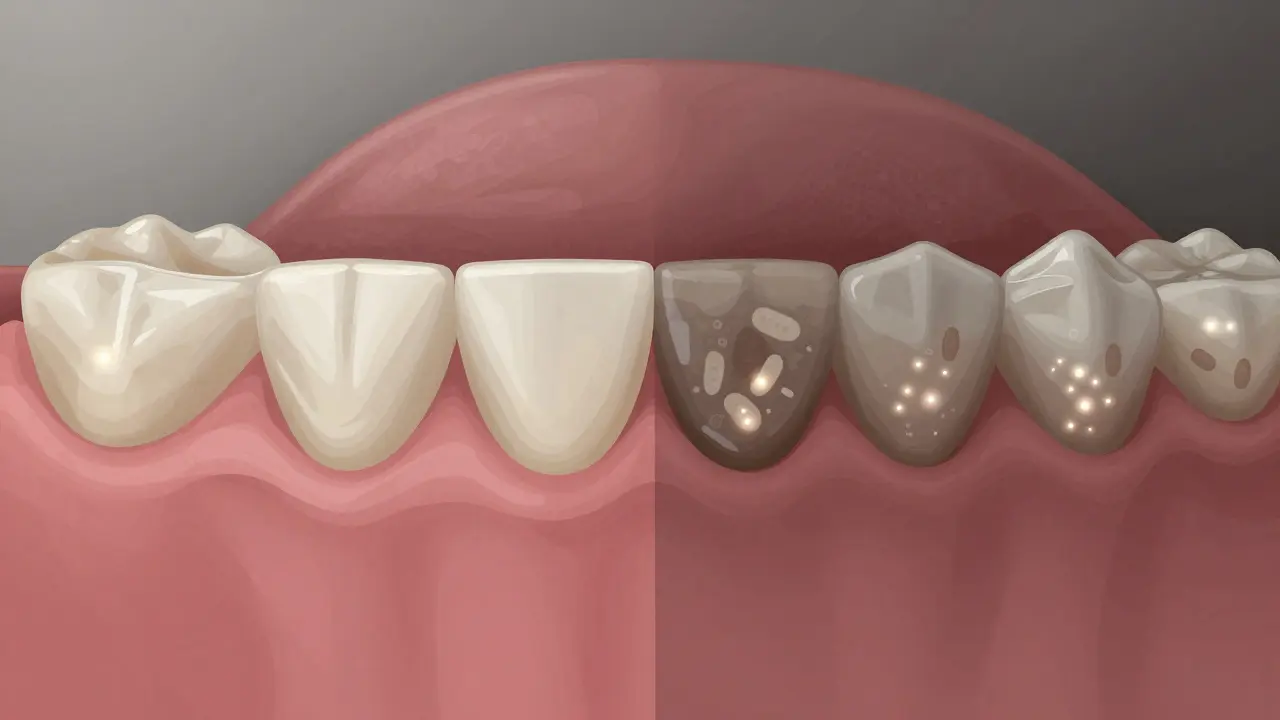

Přeměna zubního plaku na káž pod dásní během 24 hodin, znázorněno symbolicky.

Káž pod dásní způsobuje ztrátu kosti kolem zubu, zobrazeno jako postupné rozpouštění.